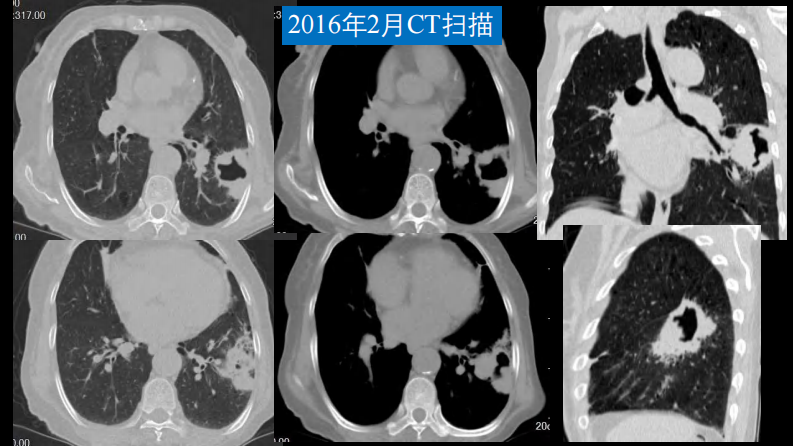

肺部空洞性病变CT与MRI.pdf